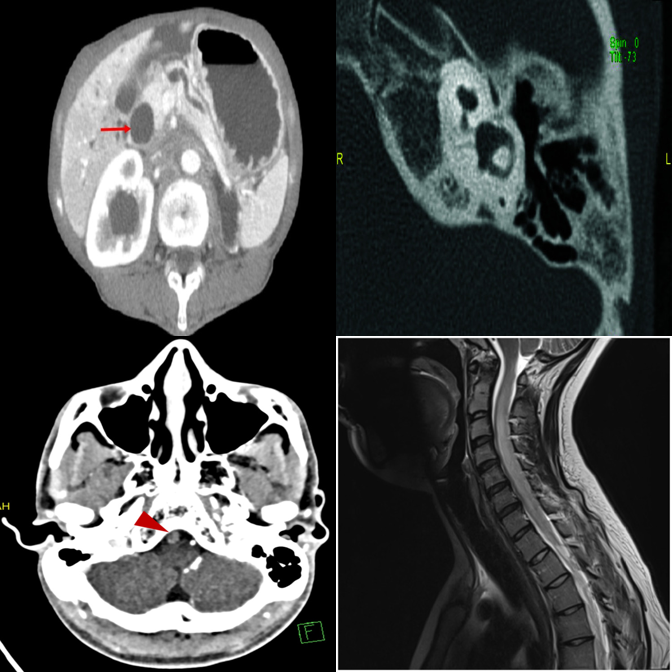

Dense 3×3 grids with 8 distractors. Systematic comparison is essential.

The dense 3×3 layout overwhelms systematic comparison — picks wrong column.

Falls back to default position under uncertainty in the dense grid.

3×3 grids universally expose shallow pattern matching.